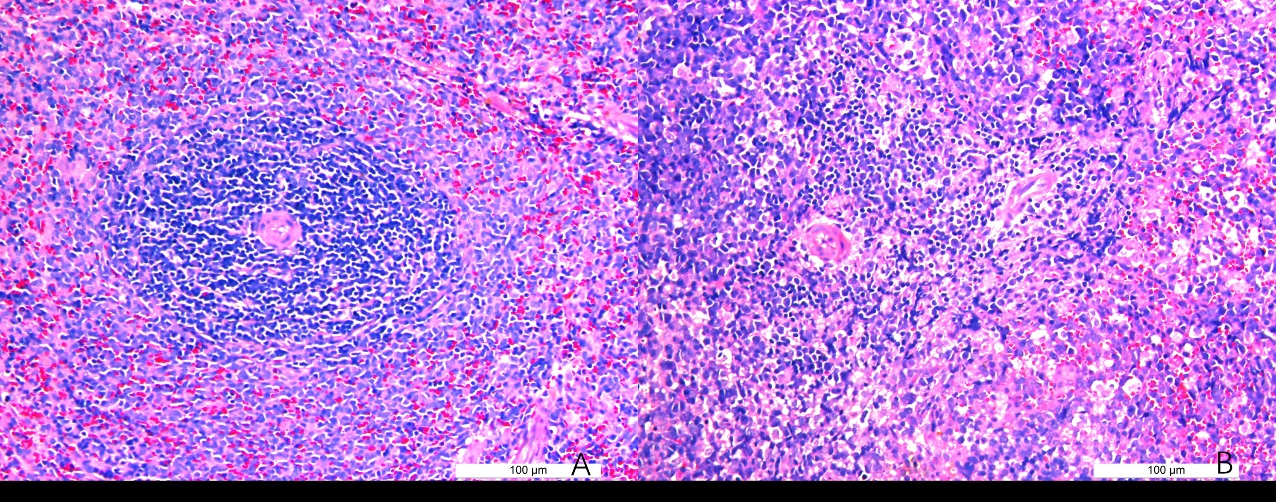

2 结果48 h各组病理结果,对照组脾组织结构正常(见图 1A )。脓毒症组脾组织见白髓结构破坏,红白髓交界模糊,多量组织细胞浸润,红髓充血(见图 1B)。差异mRNA的Volcano-plot分布图(见图 2)。相比于对照组,24 h时脓毒症组脾组织mRNA表达上调的有1 030个,下调的有935个[5];48 h组表达上调的有1 354个,下调的有1 763个。差异mRNA的聚类情况(见图 3)。GO功能分类结果(见图 4)。脓毒症大鼠脾组织部分通路相关基因表达情况(见图 5、6):脓毒症大鼠24 h,48 h脾组织关于细胞因子及其受体相互作用通路相关基因的分布图(见图 7,图 8)。脓毒症大鼠24 h,48 h脾组织关于细胞凋亡相关通路的基因分布图(见图 9,图 10)。

| 图 1 正常大鼠及脓毒症组大鼠48 h脾组织病理切片图 |

早期过度炎症反应、晚期免疫抑制系脓毒症的重要机制之一[6-7]。脾脏为人体免疫器官,在血源性抗原出现时,负责启动免疫反应[9]。脓毒症时SIRS反应可引起脾功能障碍[10]。本研究发现脓毒症48 h大鼠脾组织白髓结构破坏,红白髓交界模糊,其结构改变可能影响其免疫功能。既往对脓毒症大鼠24 h采用基因芯片分析发现部分基因表达异常[11]。若能进一步研究其早晚期的相关基因表达变化也许对脓毒症脾功能障碍有进一步的诠释。本研究采用RNA-seq技术对脓毒症大鼠早晚期脾组织行mRNA检测,是既往研究的深入,发现脓毒症早期组脾组织基因上下调数远少于晚期组,如脓毒症24 h组脾组织mRNA上调数1 030个,下调数935个,而48 h组mRNA上调数1 354个,下调数1 763个,差异明显(见图 2),符合疾病的发展过程。从图 3看,脓毒症24 h、48 h部分区域从红色趋于变浅甚至变蓝,浅蓝趋于蓝色,直观的反应脓毒症时脾脏基因表达量变化情况。从GO功能分类结果(图 4)得知,cellular processes、Environmental informationProcessing、Genetic Information Processing、Human Diseases、Metabolism、Organismal Systems相关功能基因随时间发展出现差异表达数为上升趋势。进而我们对其分析发现,脓毒症早晚期脾mRNA出现变化主要涉及细胞因子与其受体相互作用、IL-17、T细胞受体、TH1、TH2细胞分化、TNF、Toll受体、凋亡等相关信号通路。研究显示,脓毒症晚期免疫抑制可能是脓毒症患者死亡的主要原因,免疫治疗可能是未来一大趋势[12-15]。本文拟从炎症反应与细胞凋亡相关通路来阐述脓毒症脾功能障碍的相关机制。